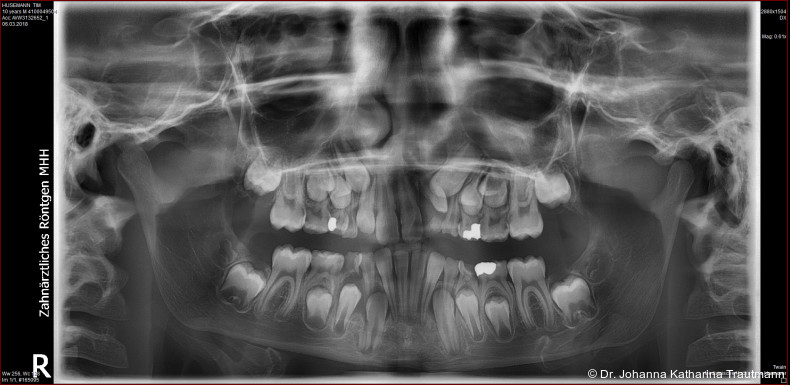

Das Fernröntgenseitenbild zeigte eine skelettale Klasse IIAnomalie mit einem Wits von 5,6 mm, bei einer tiefen Konfiguration (ML NL = 16,5°) mit bialveolär retrudierten Fronten (OK1NA = 5,9°; UK1NB = 10,4°), was sich auch in der Modellanalyse widerspiegelte. Hier zeigte sich zudem ein schmaler Oberkiefer mit multiplen Kippungen und Rotationen in der Front, einem hypoplastischem 22 sowie einer Mesialwanderung des 16. Des Weiteren zeigte sich eine asymmetrische Bisslage mit 1 PB distal rechts und ½ PB distal links bei einem Overjet von 2,5 mm sowie einem Overbite von 5 mm. Während im Unterkiefer bereits die zweite Zahnwechsel phase begonnen hatte, zeigte sich im Oberkiefer noch kein Wechsel in den Stützzonen. Gerade bei Patienten mit Spaltbildungen ist eine engmaschige Überwachung des Durchbruchs der oberen Eckzähne essenziell. Während bei der Allgemeinbevölkerung die Prävalenz von verlagerten Eckzähnen bei ca. 2,8 Prozent liegt2, ist diese bei Patienten mit Lippen-Kiefer-Gaumen-Spalten um den Faktor 10 erhöht.3, 4 Als klassische Risikofaktoren gelten zudem Platzmangel, transversale Enge aber auch Fehlstellungen, Nichtanlagen oder Hypoplasien der zweiten Schneidezähne. Diese übernehmen normalerweise die Funktion der Leitschiene für den S-förmigen Durchbruch der Eckzähne. Im vorliegenden Patientenfall kommen also mehrere Risikofaktoren für eine Verlagerung zusammen, was die rechtzeitige Diagnostik zur Abklärung einer Durchbruchsproblematik rechtfertigt. Da im Spaltbereich auch zusätzlich ein ausgeprägtes Knochendefizit vorliegen könnte, sollte auch immer die Option einer sekundären Osteoplastik abgewogen werden, deren Indikation und Timing optimal zum Durchbruch der Canini angepasst werden sollte.5

Zur genaueren Diagnostik der Lage beziehungen der Eckzähne und des Knochenangebotes im Spaltbereich kann neben den kieferorthopädi schen diagnostischen Unterlagen laut der S2 kLeitlinie Dentale digitale Volumentomografie6 auf eine dreidimensionale Bild gebung zurückgegriffen werden. In dieser zeigte sich eine vestibuläre Verlagerung des 13, eine palatinale Verlagerung des 23, sowie ein deutliches Knochendefizit im Spaltbereich mesial des hypoplastischen 22 (Abb. 2). Nach Auswertung der 3D-Daten erschien aufgrund der palatinalen Lage des 23 eine invasive Operation wie eine sekundäre Osteoplastik keinen entscheidenden Vorteil für die weitere Be handlung zu haben. In Rücksprache mit der Mund-Kiefer-Gesichtschirurgie der UMG wurde daher auf die OP verzichtet und initial die kieferorthopädische Therapie in den Vordergrund gestellt.

Positiv hervorzuheben ist hingegen der er zielte Knochen erhalt beziehungsweise der partielle Attachmentgewinn im Bereich der Spalte. Wie sich in den Verlaufskontrollen der OPGAufnahmen erkennen lässt, führte die Bewegung der Zähne 21 und 22 in den Spaltbereich zu einer deutlichen Verbesse rung der knöchernen Situation. Obwohl das Knochenniveau nicht vollständig physiologisch ist, konnte ohne zusätzliche Knochenaugmentation eine stabile Knochen und Gewebesituation erreicht werden. Dass ein Attachmentgewinn durch gezielte kieferorthopädische Zahnbewegung möglich ist, wurde bereits von Melsen et al.22 beschrieben. Während sich die meisten nachfolgenden Studien auf parodontal vorgeschädigte Gebisse konzentrierten, zeigt der vorliegende Fall eine mögliche Übertragbarkeit dieser Mechanismen auf Spaltpatienten mit moderatem Knochendefizit.